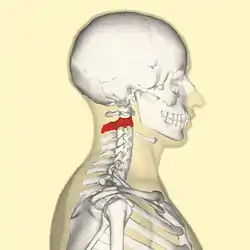

Position of axis (shown in red) | |

In anatomy, the axis (from Latin axis, "axle") is the second cervical vertebra (C2) of the spine, immediately inferior to the atlas, upon which the head rests.